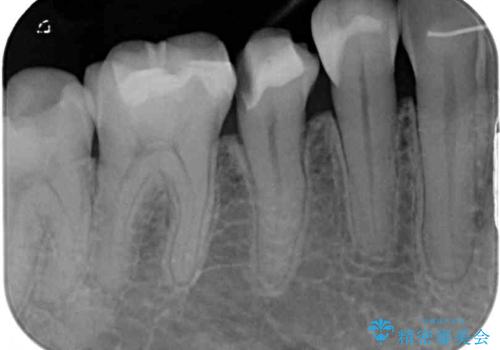

- 他院にて治療した詰め物が欠けてしまった事を主訴に来院された患者様です。

詰め物の範囲が大きく、部分的な詰め物では再び割れてしまうリスクが高いため、

オールセラミッククラウンにて補綴することとしました。